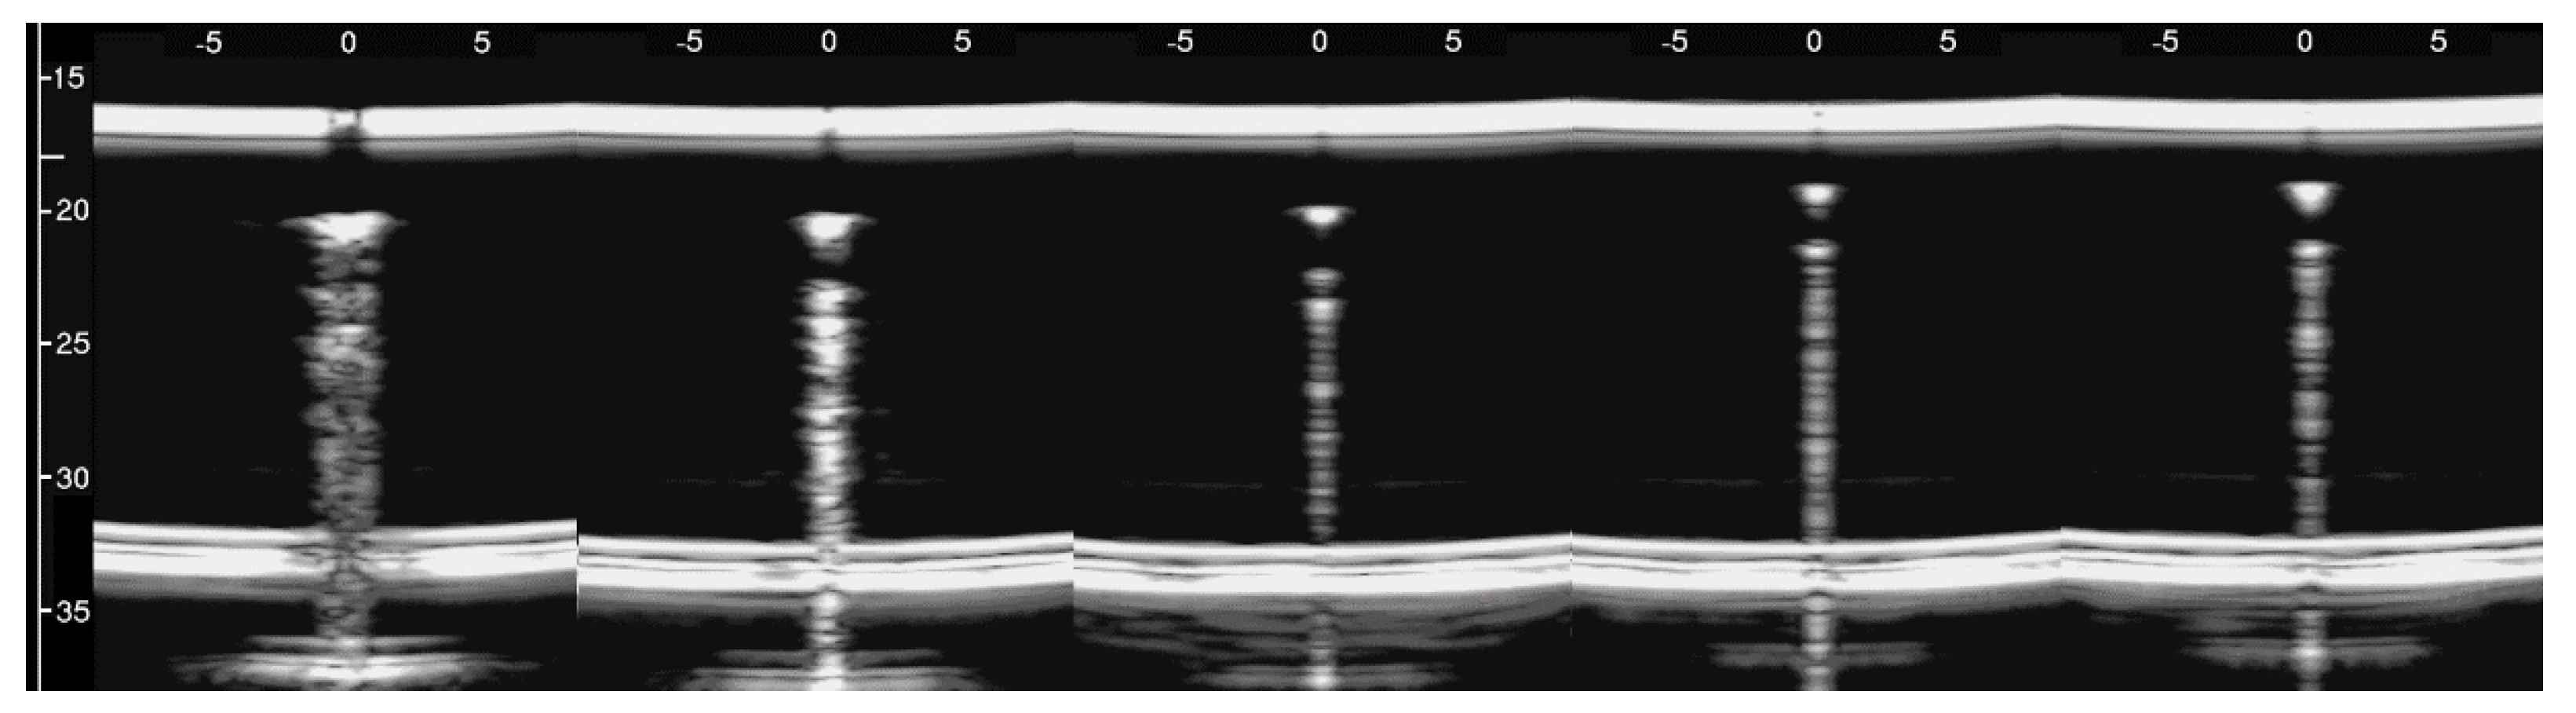

However, the box allows the examination of numerous other configurations. Figure 7 shows some configurations which were tested and the obtained artifacts. Here, it can be observed how traps with the same input channel provide different artifacts as the shape of the trap changes. Artifact A was obtained with three staggered air cylinders. The artifact is short, and it is the only one that shows the characteristic modulation of cardiogenic artifacts [7,22]. The modulation is most likely related to the simplicity of the trap which favours the constructive sum of the echoes, while its length is not easy to interpret. Artifacts B and D are generated by configurations of air cylinders which form two channels with rough lateral surfaces and the different lengths suggest their probable origin. The two artifacts are probably generated by multiple reflections between the walls of the channels during the propagation of the acoustic wave from the top to the bottom of the two channels. Artifact C is generated by a configuration of cylinders similar to that illustrated on the left of Figure 1 with cylinders of a larger diameter. Here, it can be observed how a larger trap with a more complex internal geometry than trap A provides a longer and more confused artifact. Artifact E was generated by a configuration of air cylinders obtained by eliminating the two cylinders that form the input channel of the trap that generated artifact C. This example shows how very different artifacts can be obtained when varying the shape and the size of the access channel. The F artifact is particular since in this case the US energy can be transmitted to the trap through the two small (0.5 mm large) lateral channels and through the larger (2 mm large) central channel. In this case, the artefactual information can be seen as three close but different artifacts or as a single complex artifact.

Figure 7. Six different arrangements of air cylinders immersed in agar gel and the obtained artifacts are shown. The black dots indicate the position of the air cylinders.